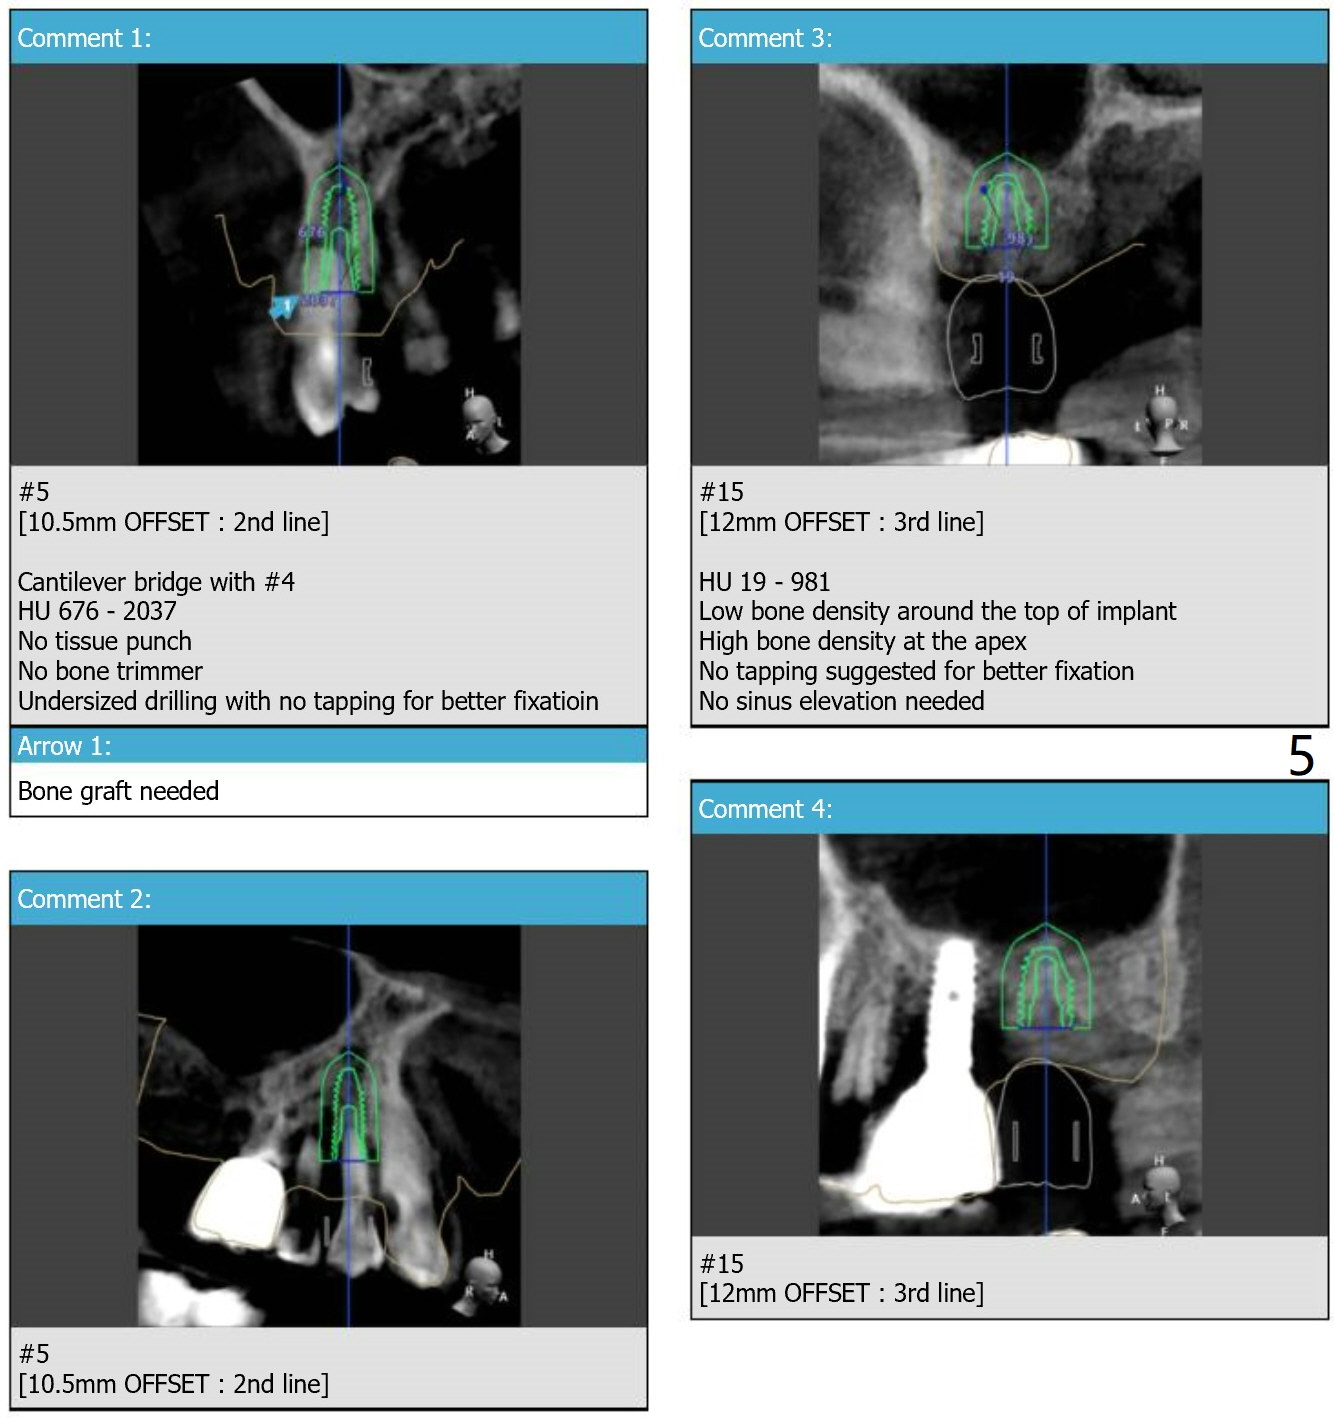

Because of the narrow space at #4 and 5, an implant will be placed slightly distal of #5 site and a cantilever FPD will be made at #4 and 5.